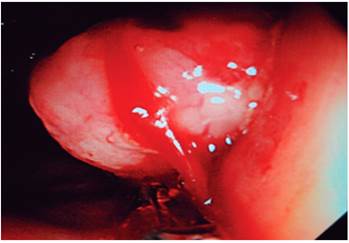

La colonoscopia reveló una lesión de aspecto tumoral a nivel de la válvula ileocecal, redondeada de unos 4 cm de tamaño y del mismo color que la mucosa circundante; se apreció el signo de la tienda de campaña, que es la elevación de la pared intestinal con base ancha y vértice romo, sin pedículo con conservación de la mucosa intacta (Figuras 3 y 4). Se tomó una biopsia para el estudio histológico, que informó la presencia de un carcinoma neuroendocrino poco diferenciado grado III. La inmunohistoquímica fue positiva a enolasa neuroespecífica (NSE), sinaptofisina y Ki 67 (Figuras 5, 6 y 7).